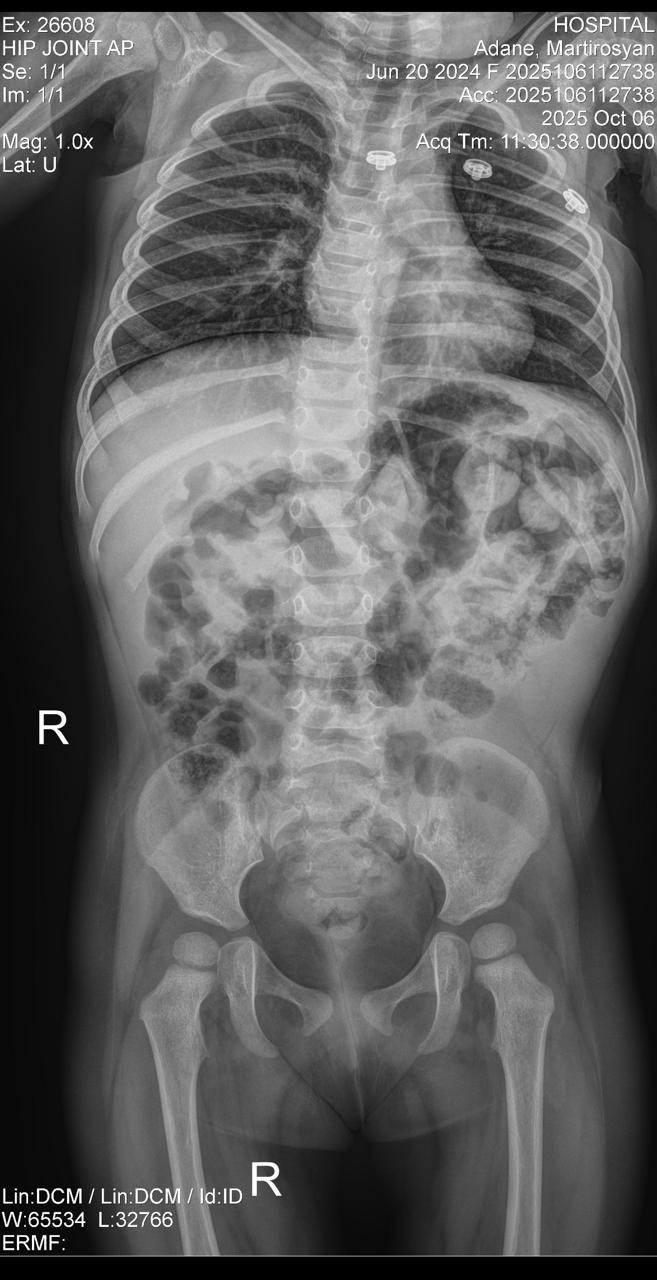

Martirosyan Adana Mkrtichi is a 1-year-8-month-old baby girl from Armenia born with spina bifida, a severe condition affecting her spine and nervous system.

Adana cannot walk, stand, or move on her own. She also cannot have bowel movements without medication. While other children take their first steps, Adana is still waiting for the chance to take hers.

Doctors confirmed that she needs complex spinal surgery, including the implantation of a spinal tube. This life-changing treatment requires multiple surgeries as she grows, but it is not available in Armenia. Her only hope is specialized pediatric neurosurgery in France.